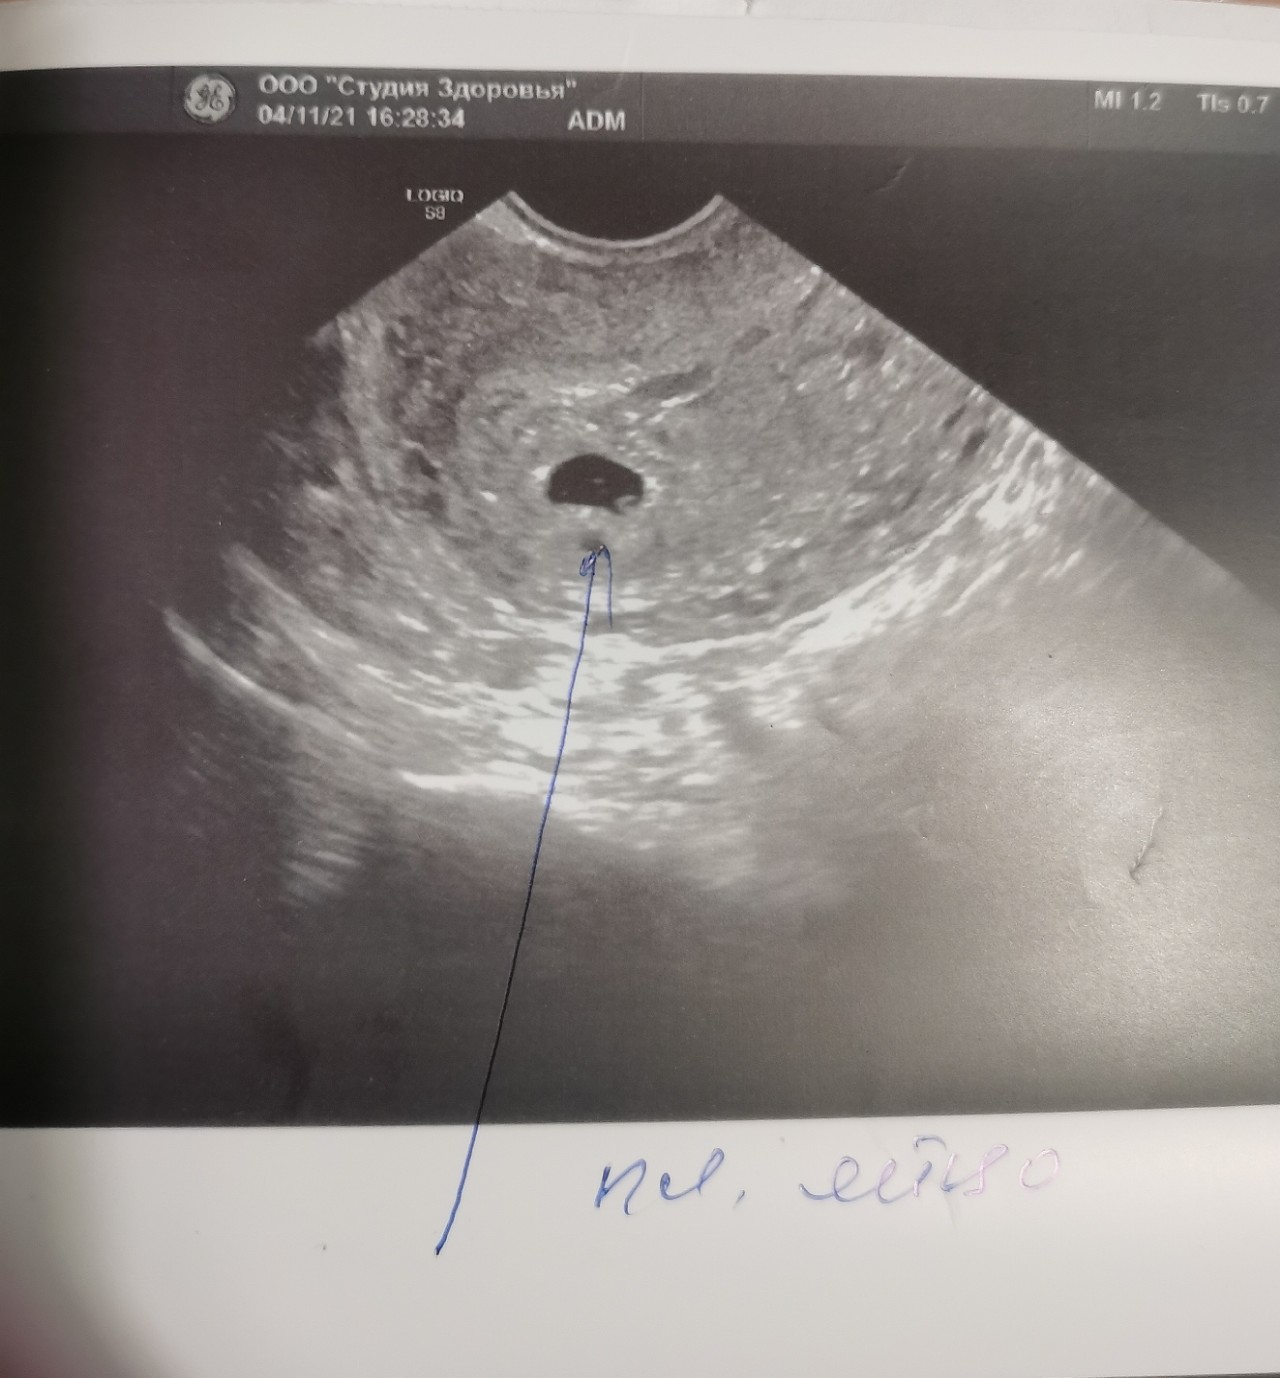

Медицина и диагностика: Инвазивный пузырный занос на УЗИ